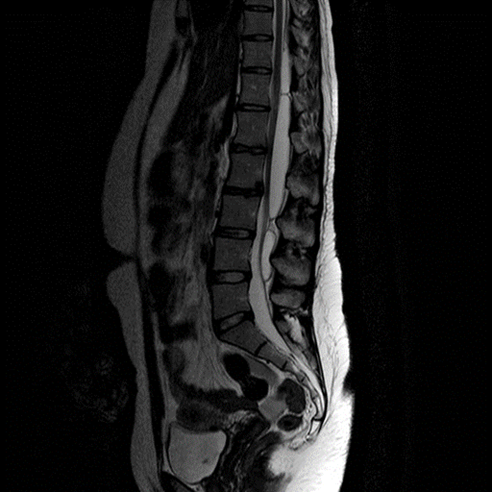

Learn MoreElective Spinal Disease

Degenerative spinal disease, atlantoaxial subluxation, spondylolisthesis and spondylitis

Learn MoreSpinal Trauma

Acute spinal injury management including spinal cord injury management both acutely and in the longer term. There are some complimentary sessions in the rehabilitation module.